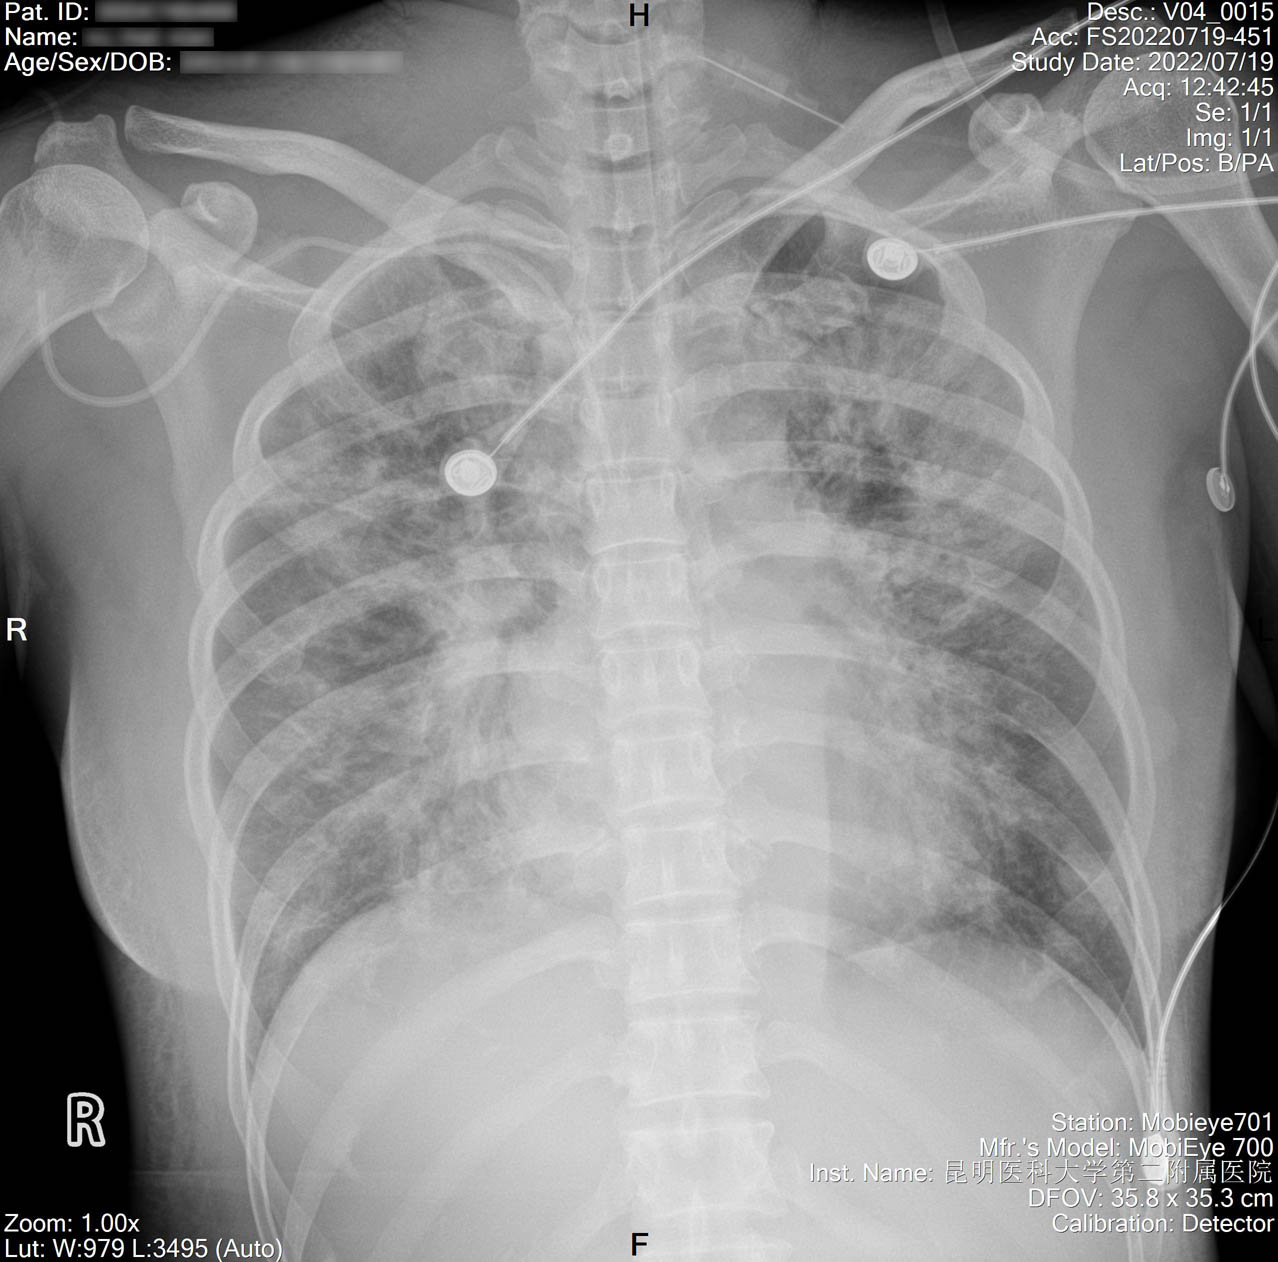

2022-07-19_胸片